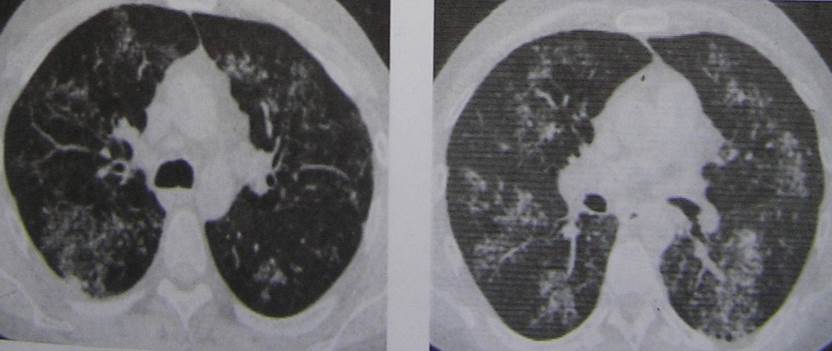

Иллюстрации по теме очагового и инфильтративного туберкулеза